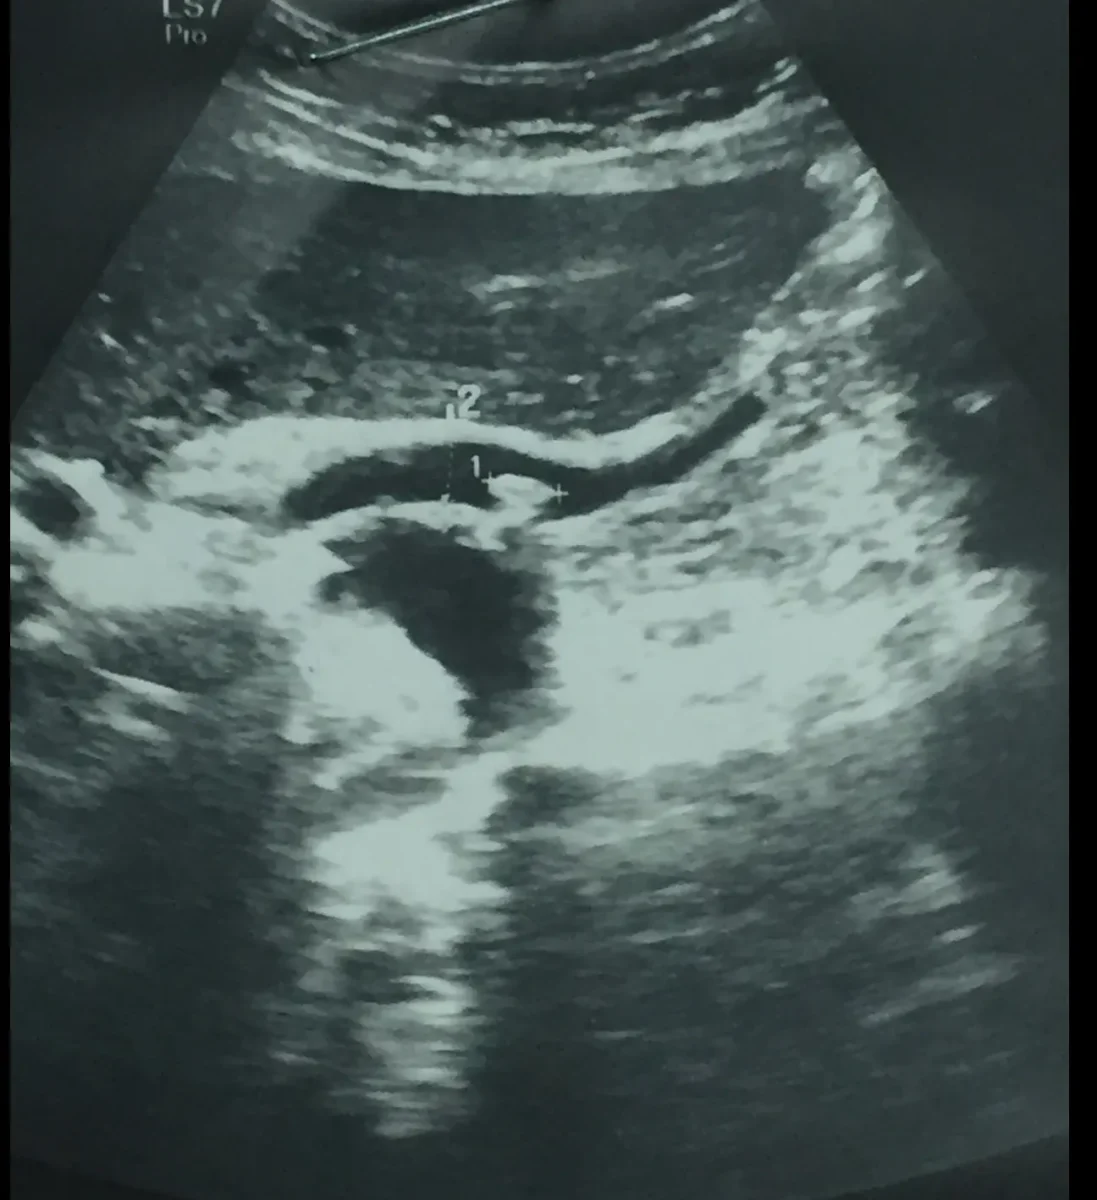

Ecográfico: la sospecha clínica de colelitiasis se puede confirmar en la mayoría de pacientes mediante la ecografía Hepatobiliar.